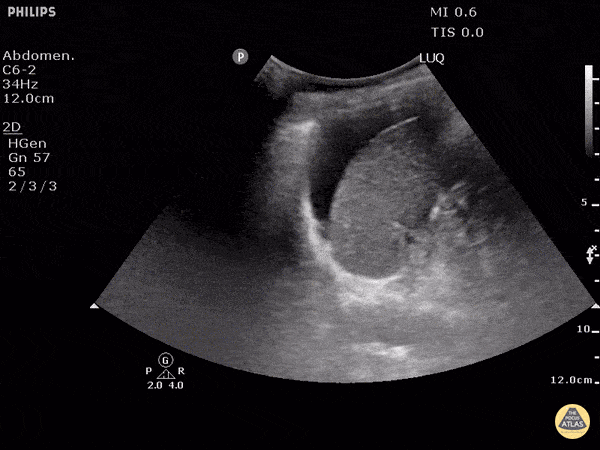

Which LUQ view represents a positive FAST (fluid present)?

The correct answer is A. Free fluid can be visualized between the diaphragm at the left side of the screen and the spleen on the right.